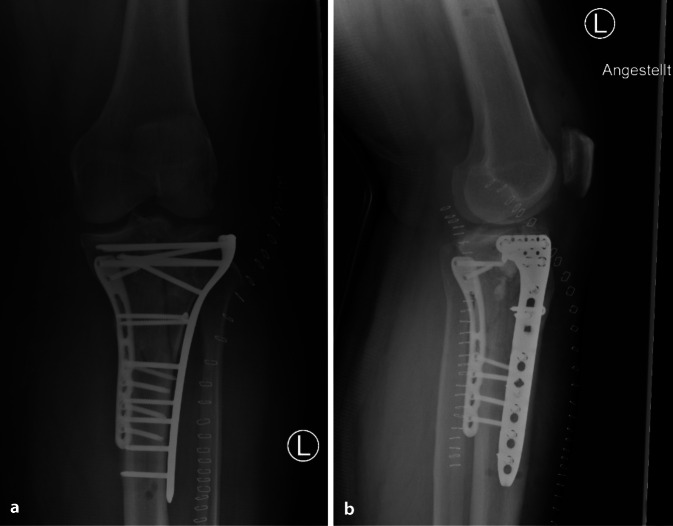

| Tibiakopffraktur Typ Schatzker VI (Abb. 4, 5) |

1. Anlage eines Fixateur externe 2. Plattenosteosynthese via dorsomedialem Zugang 3. Plattenosteosynthese via anterolateralem Zugang |